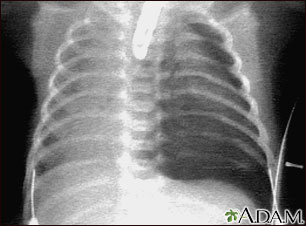

Pneumothorax occurs when air leaks from inside of the lung to the space between the lung and the chest wall. The lung then collapses. The dark side of the chest (right side of the picture) is filled with air that is outside of the lung tissue.